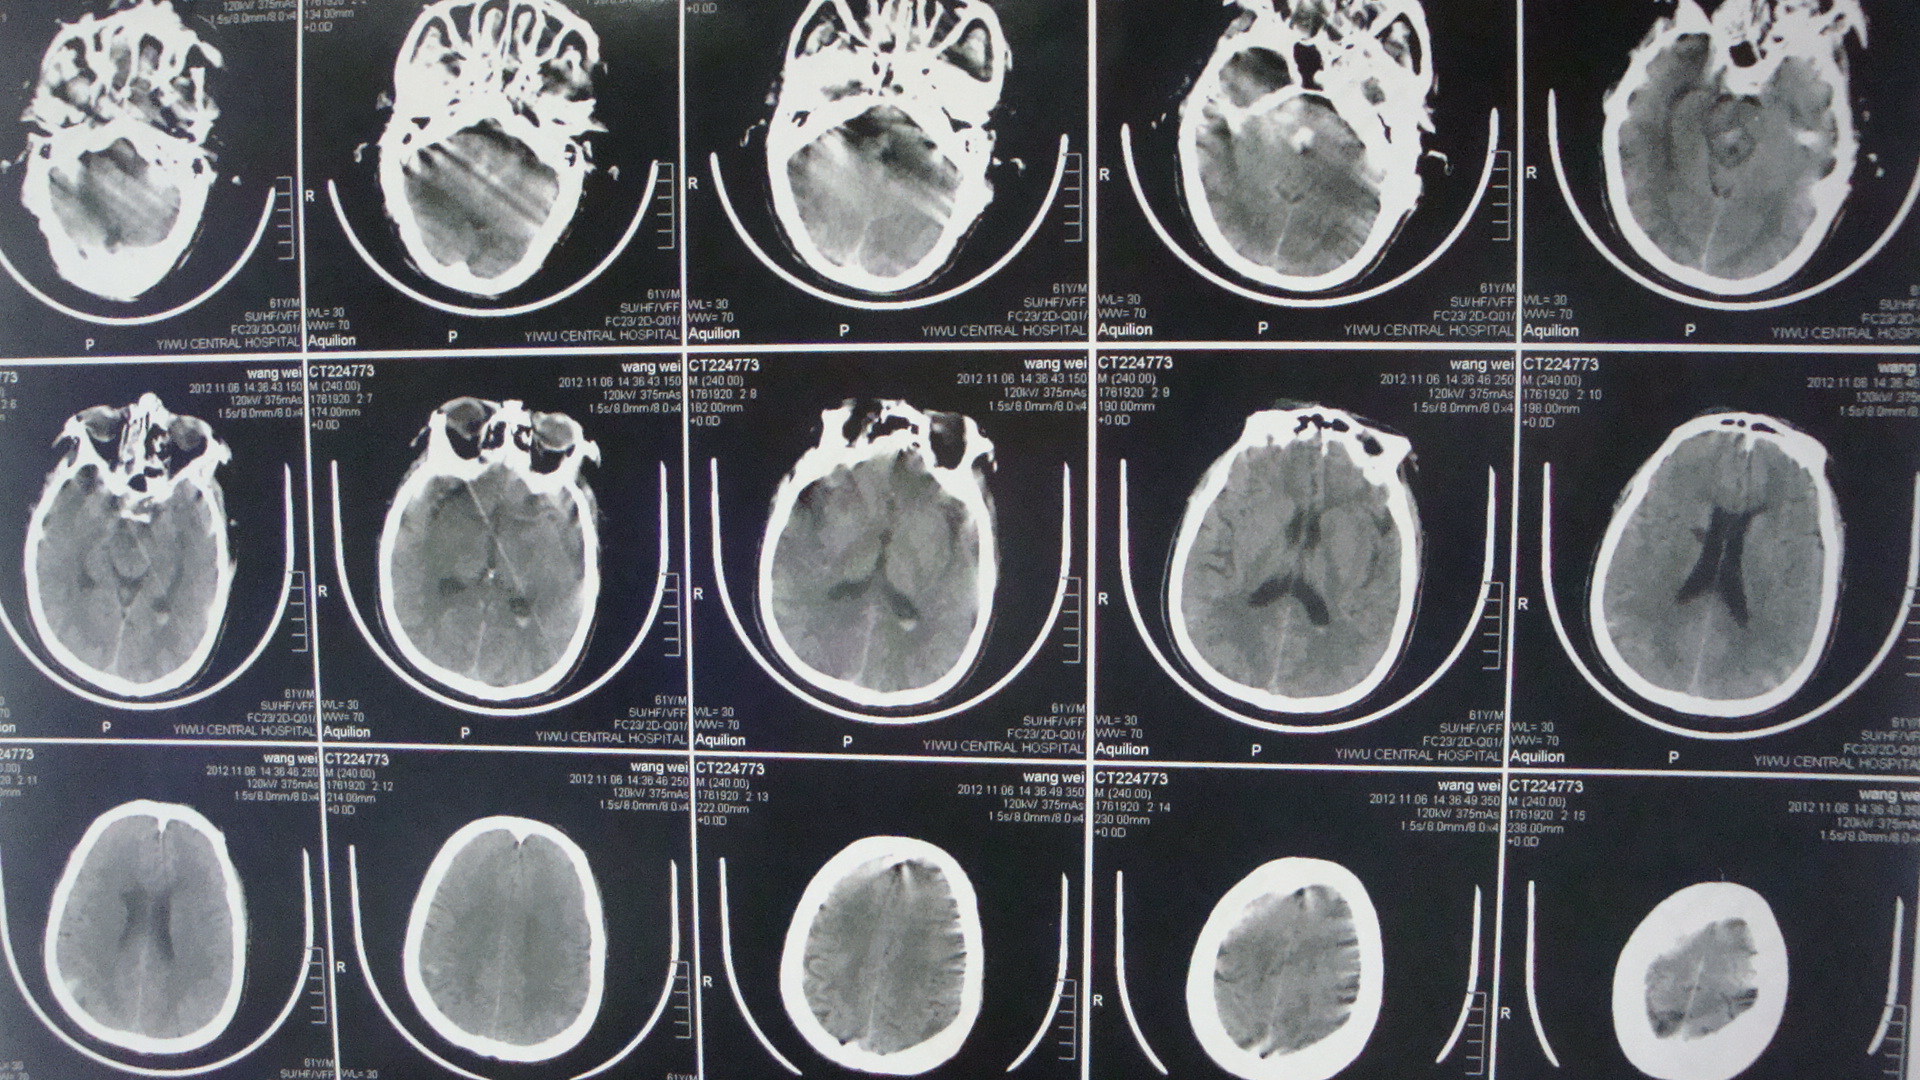

10月31日头颅CT:脑干出血

10月31日

10月6日在教授会诊处理后,病人脑干出血部位血肿有吸收。

11月6日

11月9日头颅CT:脑干血肿明显吸收,病人已经有意识了。

11月9日